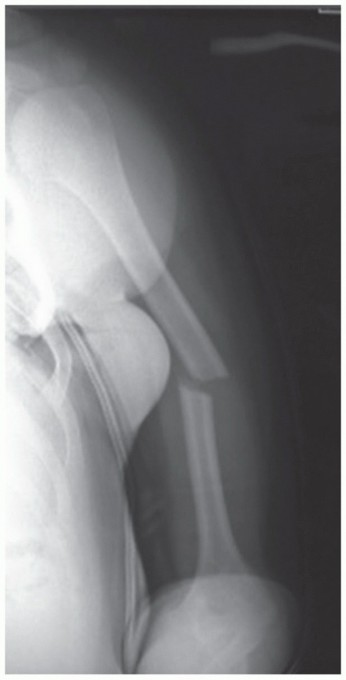

DEFINITION Humeral shaft fractures, which account for about 3% of adult fractures, usually result from a dire…